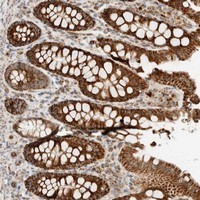

- Immunohistochemical staining of human colon with KIFAP3 polyclonal antibody (Cat # PAB21604) strong cytoplasmic positivity in glandular cells at 1:50-1:200 dilution.

- Immunohistochemistry (Formalin/PFA-fixed paraffin-embedded sections)